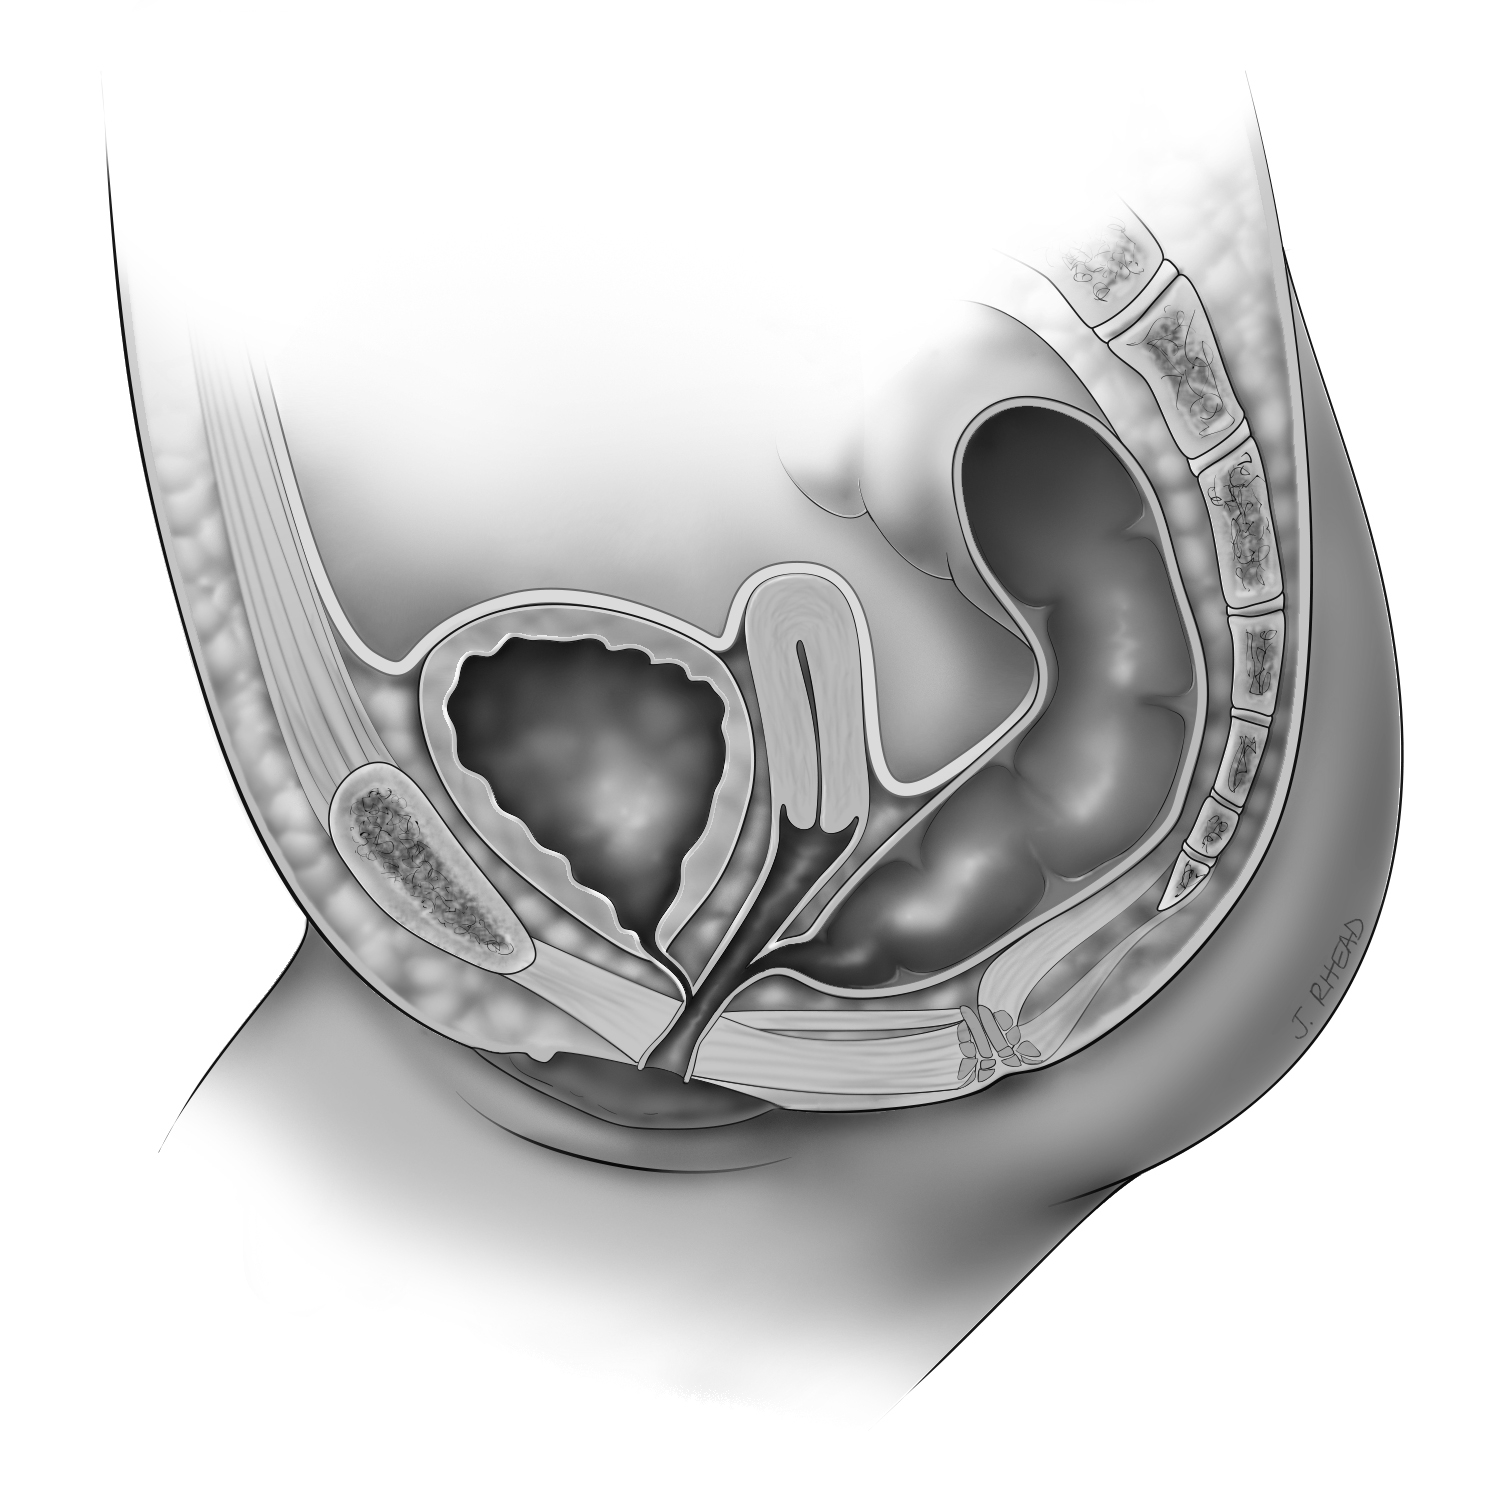

Cloaca

The rectum, urethra, and vagina fuse into a common channel, with one opening in the perineum